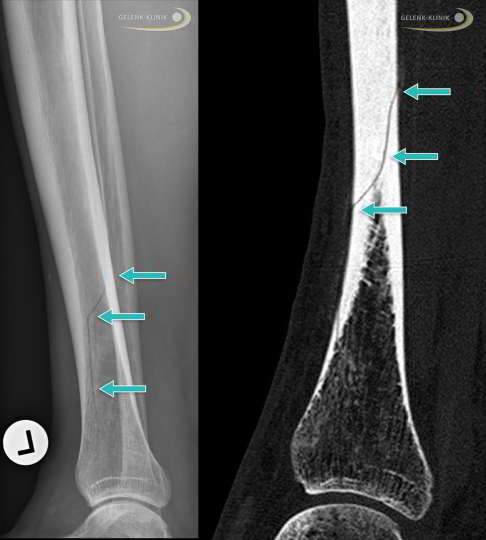

Stressfraktur des Schienbeins

Ermüdungsbrüche am Schienbein (Tibia) äußern sich sehr unterschiedlich. So kann beispielsweise das Periost (Knochenhaut) oder das im Knochen liegende Knochenmark als Stressreaktion Flüssigkeit einlagern (Ödem). Dies löst unspezifische Unterschenkelschmerzen aus. Nicht immer kommt es zu einer Verletzung der eigentlichen Knochensubstanz (Spongiosa) oder der härteren Außenschicht des Knochens (Kortikalis). Sind diese Strukturen betroffen, verläuft die Frakturlinie meist horizontal. Es können aber auch Längsrisse entlang des Schienbeinknochens auftreten. Die meisten Stressfrakturen treten im unteren (distalen) Bereich des Tibiaschaftes auf. Insgesamt betreffen etwa 50 % aller Stressfrakturen das Schienbein.

Digitale Volumentomographie (DVT) zur Diagnostik und OP-Planung

Zur Stellung der exakten Diagnose einer Stressfraktur werden häufig mehrere bildgebende Verfahren wie die digitale Volumentomographie (DVT), die Computertomographie (CT) oder die Magnetresonanztomographie (MRT) miteinander kombiniert.

Die vielversprechendste Möglichkeit zur Erkennung von Stressfrakturen im Bereich der Fußgelenke ist die digitale Volumentomographie (DVT). Dieses radiologische Verfahren macht Knochen- und Gelenkveränderungen durch die Erstellung von Schnittbildern bereits im Anfangsstadium der Erkrankung sichtbar. Häufig entstehen Stressfrakturen am Fuß im Bereich des Innenknöchels mit Beteiligung des Sprunggelenks, wo sie durch die DVT schon früh nach dem Auftreten erster Symptome erkannt werden können. Im Gegensatz zum MRT-Bild sind für die Diagnosestellung mittels DVT allerdings immer Veränderungen der Knochenstruktur notwendig, um Stressfrakturen sicher zu ermitteln. Das bildgebende Verfahren wird neben der Diagnostik auch zur Operationsplanung eingesetzt.

Operationen sind sinnvoll, wenn der Knochen nicht von alleine heilt und eine verzögerte Spontanheilung vorliegt. Dies kann beispielsweise bei einer Fraktur im mittleren Bereich des Schienbeins der Fall sein. Um die Knochenheilung zu stimulieren, wird der Knochen in einem operativen Eingriff angebohrt.